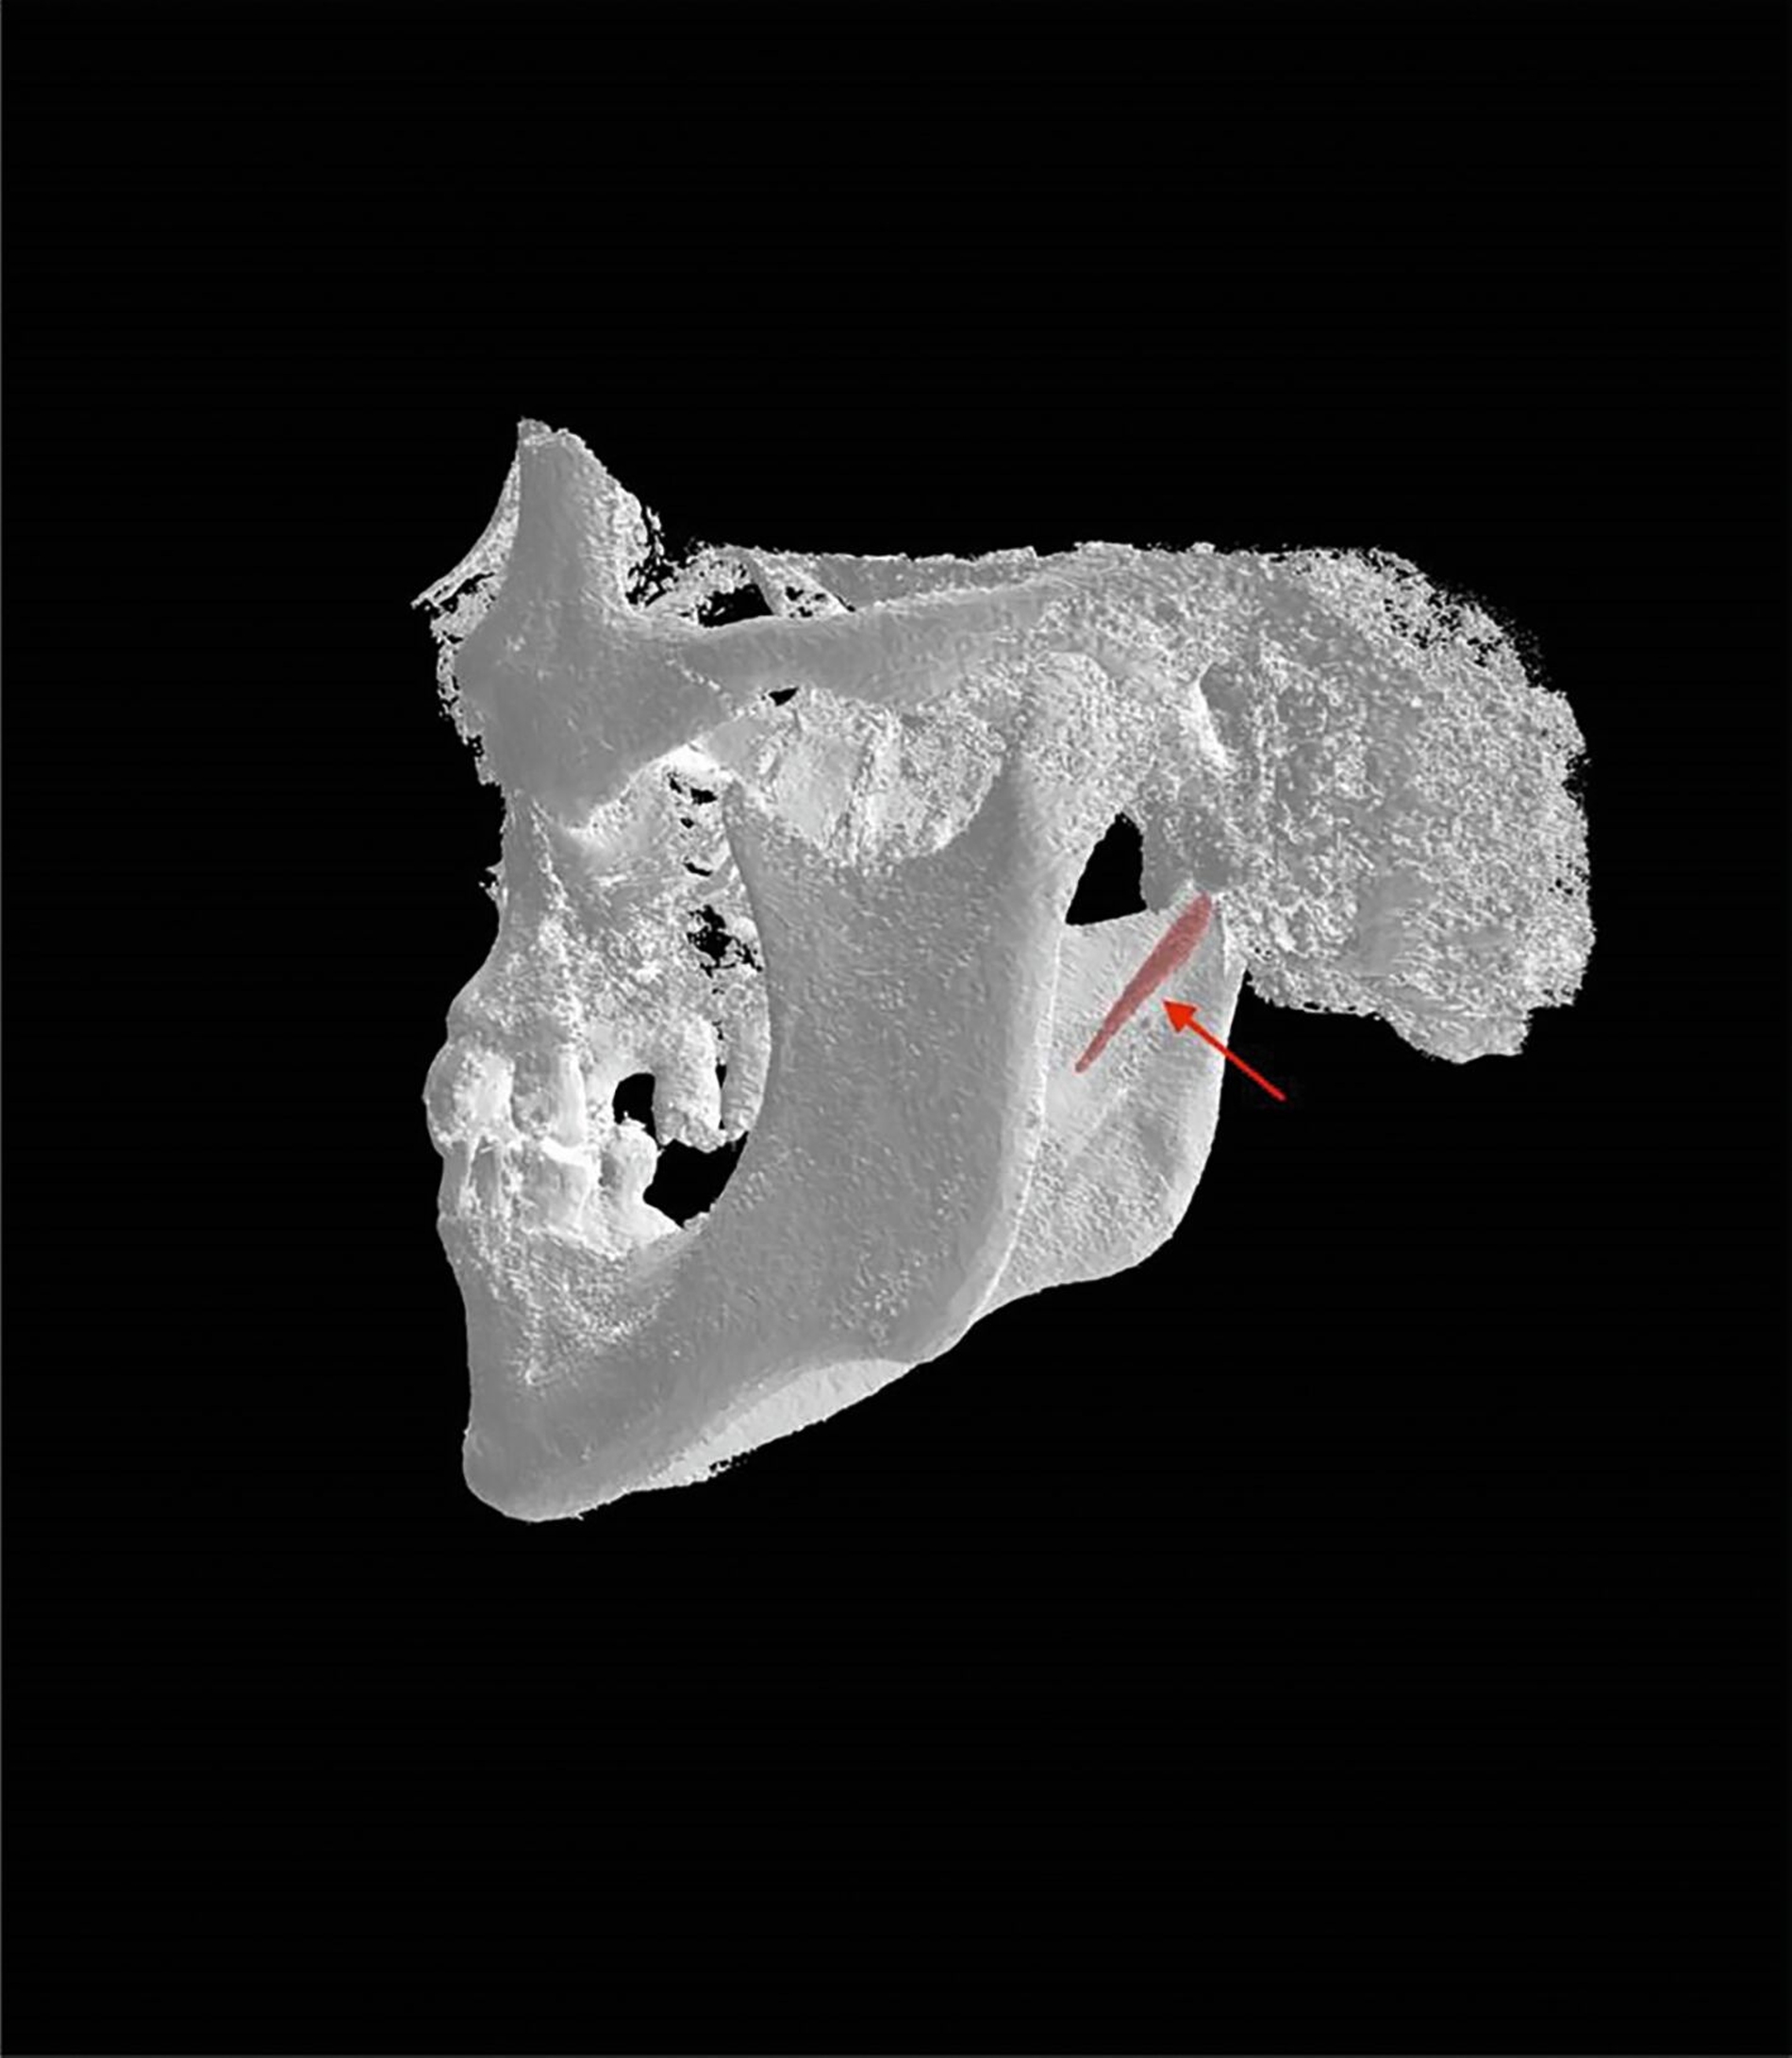

Die bildgebende Untersuchung mittels Orthopantomografie (Abbildung 1) und nachfolgender digitaler Volumentomografie (Abbildung 2) ergab eine Verlängerung des Processus styloideus beidseits, die auch im Rahmen einer dreidimensionalen Rekonstruktion dargestellt werden konnte (Abbildung 3). In Zusammenschau mit der beschriebenen Beschwerdesymptomatik wurde die Diagnose eines Eagle-Syndroms gestellt.

Der postoperative Verlauf gestaltete sich regelrecht ohne Nachblutung oder Wundheilungsstörungen. Die Mini-VAC-Drainage wurde am zweiten postoperativen Tag entfernt. Die Gesichtsmotorik linksseitig im Bereich des Mundwinkels zeigte sich leicht abgeschwächt. Eine postoperative digitale Volumentomografie zeigte die beabsichtigte Verkürzung des linken Processus styloideus (Abbildung 4). Die Entlassung folgte am dritten postoperativen Tag in zeitgerecht gutem Allgemeinzustand.